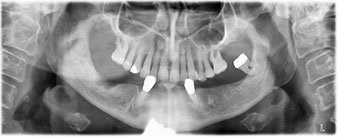

La paziente, 64 anni, presenta una dentatura residua di denti 38, 33 e 43 e una protesi combinata innestata nella mandibola (Fig. 1 e 2).

dentatura residua

Fig. 2